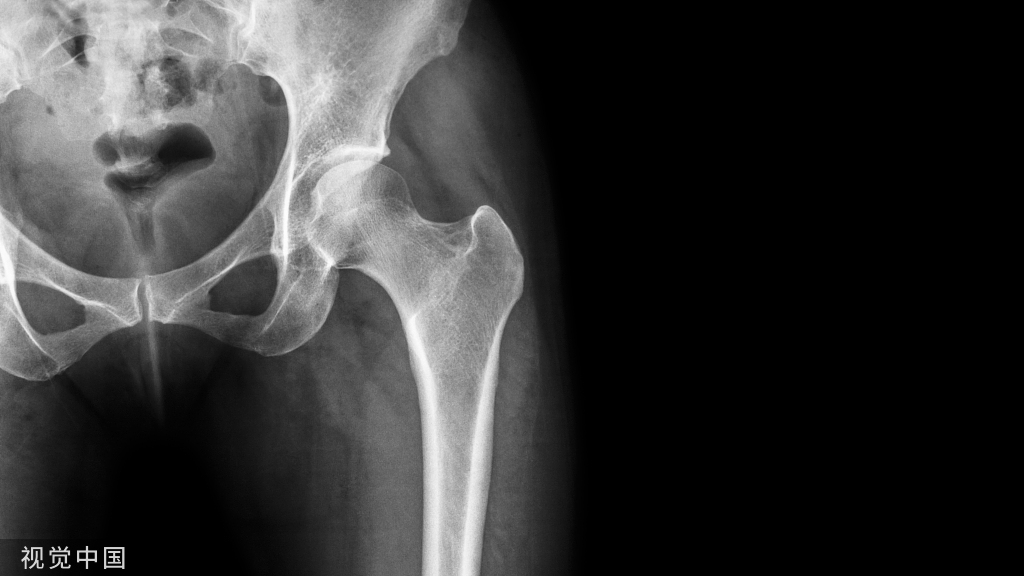

X线表现:一般呈中心性生长。可见边缘清晰的类圆形骨质破坏区,多有硬化缘与正常骨质相隔,邻近骨皮质变薄膨出,破坏区可见散在的砂粒样钙化,这是软骨瘤主要的X线表现。

CT表现:显示膸腔内异常软组织影,其内可见环形、点状或不规则钙化影,骨皮质变薄 ,边缘光整、锐利,一般无中断。增强可轻度强化。